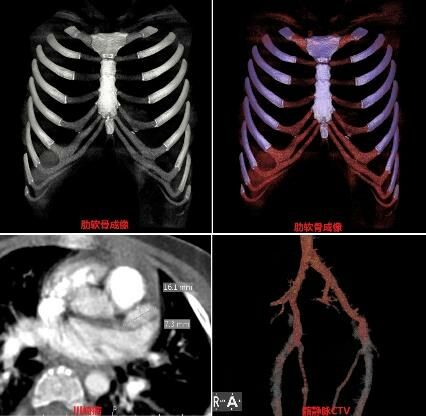

2月:为提高优质服务放射科和儿科联合开展礼仪培训活动(图3)。放射科积极和院内,院外临床沟通开展了肋软骨成像,川崎病冠状动脉CTA检查,髂静脉CTV等检查(图4)。

图4开展多项业务